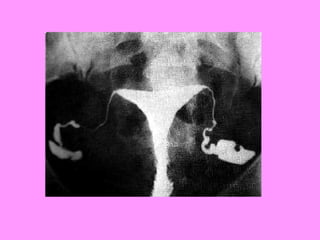

• Broad range of tests avail

– General health status checked 1st

– Pelvic examinations, ultrasound, CT scans

check for structural abnormalities

– Tubal insufflation (gas/pressure

measurement) or hysterosalpingogram (X-ray

w/ contrast material) used to check tubes

– Blood tests throughout cycle to check

hormone levels